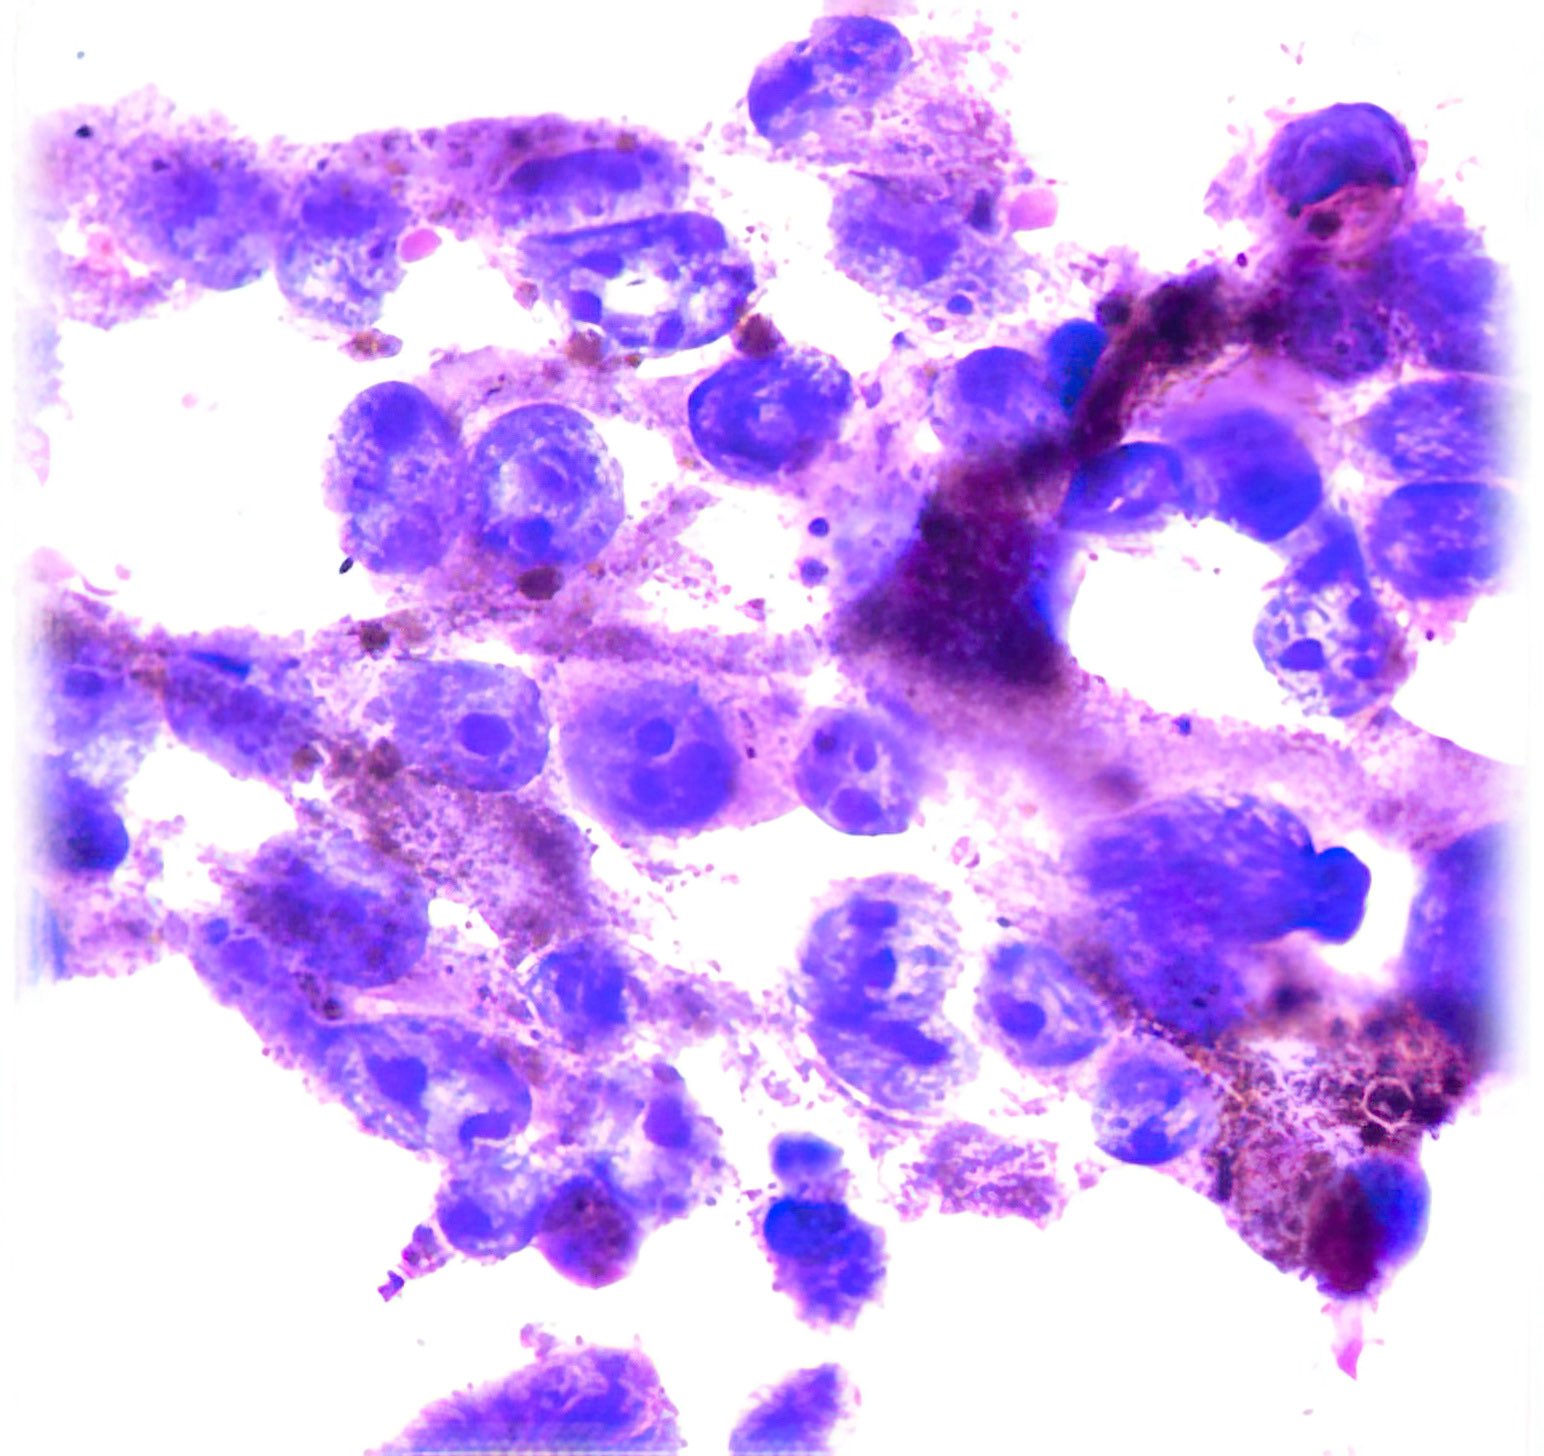

Abbildung 1 – 4: HE-Färbung; 1 – 4, original Obj. 40x, Abb. 4:

zusätzlich vergrößert

Beschreibung

Die sich teils überlagernden Zellen erscheinen meist nacktkernig oder haben nur wenig Zytoplasma. Die Kerne variieren deutlich in Form und Größe, sind grob strukturiert und zeigen vereinzelt kleine Chromozentren und Protrusionen. Im Hintergrund etwas Zelldetritus.